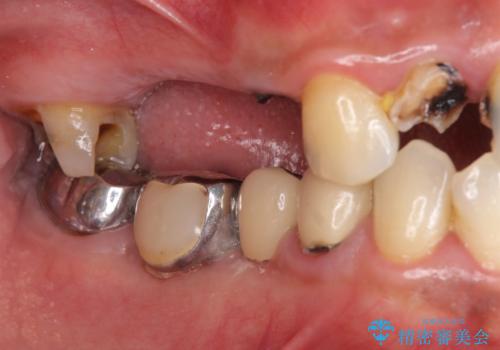

インプラント治療・セラミック治療を含む 全顎的虫歯治療

- 「 仕事が忙しく、虫歯を放置しすぎてしまった。この際全てきっちりと治したい。」と来院されました。

・歯の欠損

・虫歯

・深い虫歯

・欠損の放置による対合歯の挺出

・咬合平面の乱れ

・感染根管

以上のような問題を、徹底的な虫歯治療、歯周外科、インプラント治療、部分矯正治療、精密根管治療を用いてひとつずつ解決ししっかりと長期的に食事を楽しめるような口腔内環境の再構築を目指します。